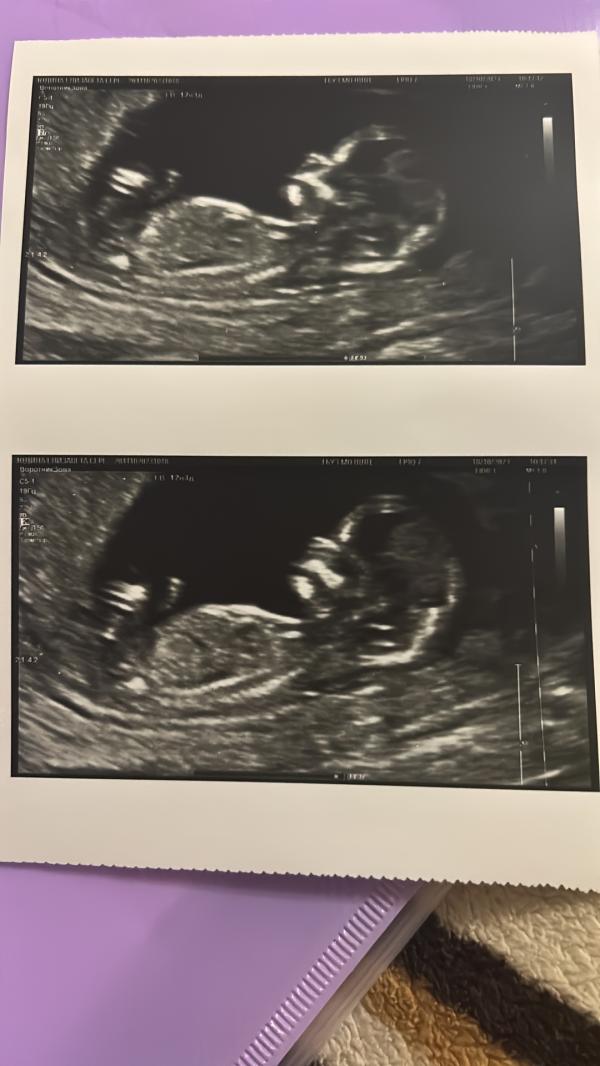

Первый скрининг позади, осталось дождаться кровь 😀 и дилемма теперь, где рожать: в Пушкино или в Щёлково ?.. есть отзывы за последние несколько месяцев ?

Нет,пол я не узнавала,либо гендер пати после 2 скрининга сделаем либо на родах узнаем,пока не решила 😁 и далеко не всегда ,если на узи все хорошо значит,что кровь будет хорошая